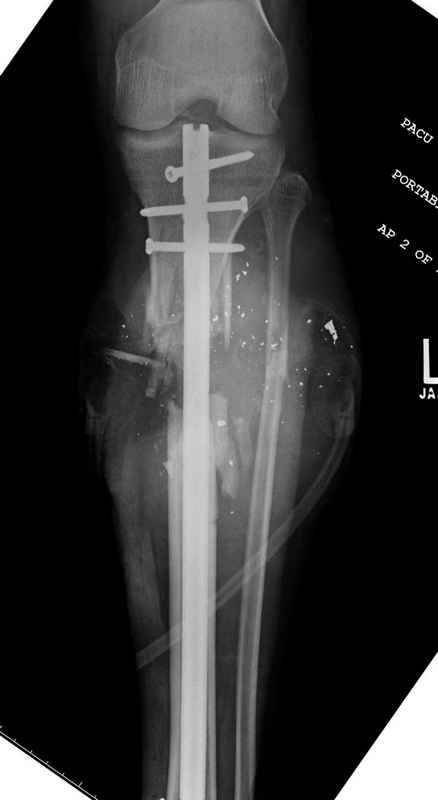

Уважаемые коллеги, Современная тактика лечения огнестрельных переломов вызывает споры. Опыты многих стран доказывает, что открытые переломы можно успешно лечить с применением внутренних металлических конструкций, включая гвозди. В западных странах более 25 лет эту методику применяют для лечения огнестрельных переломов. После применения адекватных методов по предупреждению осложнений, например, после промывания ран, огнестрельные переломы можно стабилизировать без боязни инфицирования. Здесь представлен больной 27 лет с ранениями, включая огнестрельный перелом большеберцовой кости. Стандартный аьгоритм: 11.08.09 доставлен в операционную, Irrigation&Debridment c фиксацией Наружным Фиксатором и вакуумирование VAC; службой травмы пройзведена ангиография с негативным результатом. (снимки 1-10) 14.08.09 повторная Irrigation&Debridment (чувстительственность из раны негативная) со сменой фиксации на медуллярный гвоздь и вакуумирование VAC 18.08 и 21.08.09 Irrigation&Debridment с сменой е VAC, после высеялся MRSA in thio т.е. на специальных срезах небольшое количество (11-13) 25.08.09 повторная Irrigation&Debridment. Пластик хирург не стал рисковать с Soleus flap из-за отечности, и применен Gastric flap, кожная пластика на медиальную и латеральную рану; аллографт из костных стружек с BMP. Поверхность вакуумирована VAC системой на 4 дня (14-16) Финальные снимки сделаем на днях. Djoldas Kuldjanov, MDDepartment of Orthopedic SurgerySt. Louis University Medical Center